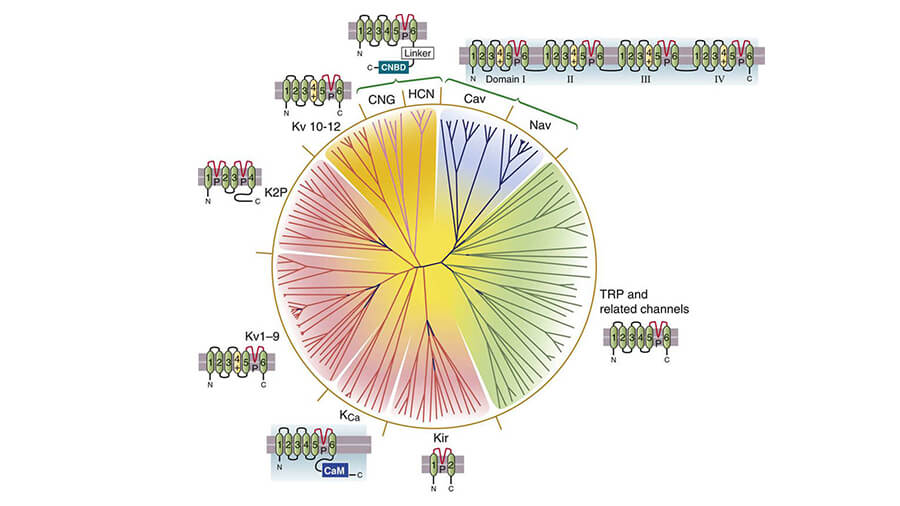

The NOVA team has been involved in ion channel research since the 1980’s. They have a long history of providing data for regulatory guidelines. For instance, we conducted the hERG screening for the original ILSI/HESI safety study which became the groundwork for the current S7B guidelines, and members of our team have been contracted by the FDA to provide ion channel screening in support of the new CiPA safety assessment guidelines. NOVA has worked with 100’s of companies along with multiple government agencies to help de-risk compounds.